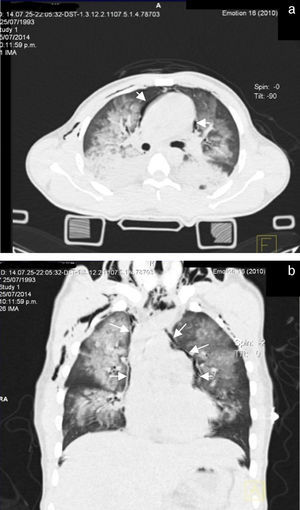

Se decide paso a quirófano por el Servicio de Maxilofacial, 48 h después de su ingreso para reducción abierta con fijación interna de fractura alveololopalatina; durante el postoperatorio inmediato presentó insuficiencia respiratoria, por lo que se realizó intubación orotraqueal para apoyo mecánico ventilatorio y se envió a unidad de cuidados intensivos; se realizó nueva tele de tórax en la que observamos la presencia de múltiples infiltrados bilaterales con relación a contusión pulmonar e imagen sugerente de neumopericardio (fig. 1).

A las 72 h de su ingreso, presentó enfisema subcutáneo en tórax anterior que se extendió a cuello, por lo que se le realizó Tc simple de tórax y de abdomen, con el hallazgo de neumomediastino, contusiones pulmonares bilaterales y neumoperitoneo (figs. 2 y 3). Continuando con apoyo mecánico ventilatorio. Se descartó lesión esofágica por esofagograma con medio hidrosoluble, al igual que lesión traqueobronquial por broncoscopia flexible; además, no se identificaron datos de irritación peritoneal, por lo que se establece como causa de neumomediastino y neumoperitoneo el efecto Macklin.

En el caso de sospecha de neumomediastino, el estudio de gabinete inicial es la radiografía de tórax frontal y lateral, que incluya la región cervical, y en este estudio se pueden identificar el neumomediastino en más del 90% de los casos9. Los signos radiográficos sugestivos de neumomediastino incluyen un trazo radiolúcido que delinea las estructuras mediastinales (más evidente craneal al corazón en el lado izquierdo), eleva la pleura mediastinal y con frecuencia se extiende al cuello o a la pared torácica. En una proyección lateral, este trazo radiolúcido puede delinear la aorta ascendente, el arco aórtico, las áreas retroesternal, precardiaca, periaórtica y peritraqueal. Otros signos radiográficos incluyen el «signo de diafragma continuo», que es gas mediastinal que delinea la superficie superior del diafragma y separa este del corazón; el «signo V de Naclerio», que presenta gas delineando el margen lateral de la aorta descendente y que se extiende lateralmente entre la pleura parietal y la porción medial del hemidiafragma izquierdo y el «signo del anillo alrededor de la arteria», en el cual el gas rodea la porción mediastinal extrapericárdica de la arteria pulmonar derecha10,13.

Los datos radiográficos indirectos incluyen el enfisema subcutáneo torácico y cervical, neumopericardio, neumorretroperitoneo y neumoperitoneo. Se debe buscar intencionadamente la presencia de neumotórax, que puede estar presente hasta en el 84% de los pacientes. La presencia de neumotórax en pacientes con neumomediastino no necesariamente indica lesión de algún órgano del mediastino; de hecho, es un fuerte indicador negativo de lesión esofágica o asociación con lesión de vía aérea10. En el caso clínico que presentamos, hubo evidencia de neumomediastino asociado a neumotórax, sin lesión esofágica ni de la vía aérea demostrada.

En los casos en que la radiografía de tórax es normal (menos del 10%), el estudio de elección es la Tc, que es considerado el «estándar de oro», aun en pacientes con hallazgos radiográficos sugestivos1,10. El efecto Macklin aparece como una colección lineal de aire contigua a la vaina broncovascular y los hallazgos característicos de enfisema intersticial por efecto Macklin, se presentan como una tríada de: 1) enfisema intersticial, 2) a bronquio, y 3) a vaso sanguíneo pulmonar3,16. La Tc respecto al neumomediastino y al neumoperitoneo tiene una alta sensibilidad (> 95%) y especificidad (> 85%) para descartar lesión mayor de tracto aerodigestivo; sin embargo, siempre se debe descartar la posibilidad de lesión esofágica o traqueal con otros métodos diagnósticos10.